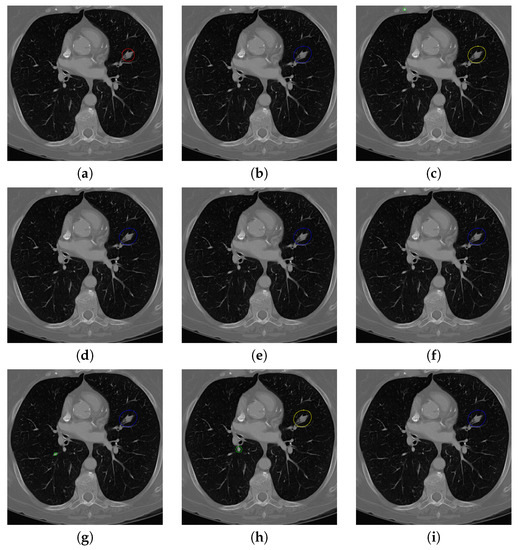

Figure 17. The result of detecting pulmonary nodules by different methods on one example image in LUNA16 dataset. Red circle represents the ground truth region of nodules, blue circles represent the correct estimation of pulmonary nodules, green circles represent the over-detected nodules, while yellow circles denote the nodules being omitted. (ai) are: ground truth nodule in the given chest CT image, nodule detected by 3D-FCN, MR-CNN, 3D-UNET, PRN-HSN, DCNN, CLAHE-SVM, MASK-RCNN and our proposed method.

Figure 17 and Figure 18 illustrates the performance of pulmonary nodule detection by different methods on two example images in the LUNA16 dataset. In addition, Figure 19 and Figure 20 illustrates the performance of pulmonary nodule detection by different methods on two examples images in the TianChi dataset. As marked by green circles in Figure 18b,c and Figure 19c, the 3D-FCN and MR-CNN directly detected the nodule candidates from the original CT image without pre-processing, resulting in the incorrect determination of non-nodule tissue outside lung as nodule since the outside-lung organs are not filtered out from the nodule candidates. The 3D-UNET and PRN-HSN add the lung parenchyma region segmentation stage before detecting the nodule candidates inside-lung, so they provide better performance than 3D-FCN and MR-CNN in decreasing the over-estimation rate. However, they still suffer from unsatisfactory results for the following reasons: (1) the lung parenchyma segmentation is generated by simple thresholding with morphological operations so the near-edge regions are lost, shown as the one marked by yellow circle in Figure 20d,e; (2) the convolution kernel used in nodule candidate detection of 3D-UNET is with a small receptive field to learn global features from the image, so it is likely to confuse some small tissues as true nodules with small sizes, shown as the one marked by green circle in Figure 18d and Figure 20d; and (3) the proposed hierarchical saliency network (HSN) in PRN-HSN for nodule candidate classification omits the information with different resolutions, resulting in that the small-size nodule within the weakened, low-resolution region cannot be correctly recognized, as shown by the yellow circle in Figure 18e. The DCNN method simply applies the Faster RCNN method to provide good performance with low computational cost, but it may omit the nodules on the parenchymal edge shown as yellow circles in Figure 20f. CLAHE-SVM method adds a contrast-enhancement pre-processing before the nodule detection, leads to better performance on detecting nodules in the low-contrast region. However, it is easily to over-enhance the small-size tissues and over-estimate them as nodules, as shown by the green circles in Figure 19g andFigure 20g. The detection is also implemented over the whole image, so the nodule on the parenchyma edge may be under-estimated show by the yellow circle in Figure 20g. The Mask-RCNN method provides better effects than the above methods because of the good performance of Mask-RCNN in object detection. However, the performance is not stable for the small-size tissues and the irregular-shape nodule, shown by the green circles in Figure 17h and Figure 19h, and the yellow circle in Figure 19h. The proposed method takes the advantage of a series of U-Net-like networks to perform the nodule detection following a “coarse-to-fine” order of inside-lung region detection, nodule candidate detection and nodule determination. The U-Net network is modified by embedding inception structure, replacing the convolution and pooling by dilated convolution, and adapting multi-scale pooling and multi-resolution convolution connection, for different requirements of the three stages, respectively. Moreover, it makes use of the MSE loss, VGG-19-based perceptual loss as the complement of dice loss to optimize the whole framework. Therefore, as shown in Figure 17i, Figure 18i, Figure 19i and Figure 20i, the proposed framework provides superior performance on pulmonary nodule detection with low over-estimation of non-nodule tissues at the same time.